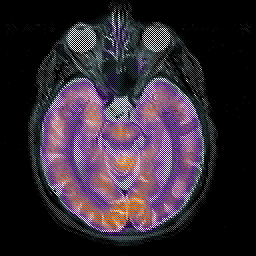

Alzheimer's disease, overlay -- Slice #18

[Home][Help][Clinical][Tour 1][Tour 2] Slice 18